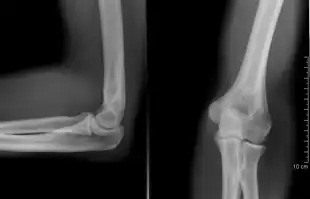

Left: Lateral X ray of a dislocated right elbow

Right: AP X ray of a dislocated right elbow

Normal radiograph; right picture of the straightened arm shows the carrying angle of the elbow

When the arm is extended, with the palm facing forward or up, the bones of the upper arm (humerus) and forearm (radius and ulna) are not perfectly aligned. The deviation from a straight line occurs in the direction of the thumb, and is referred to as the "carrying angle".[22]